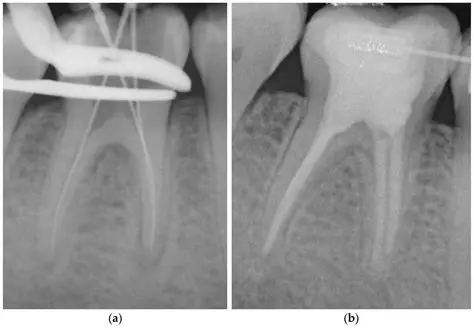

Analyze the Quality of Root Channel Filling